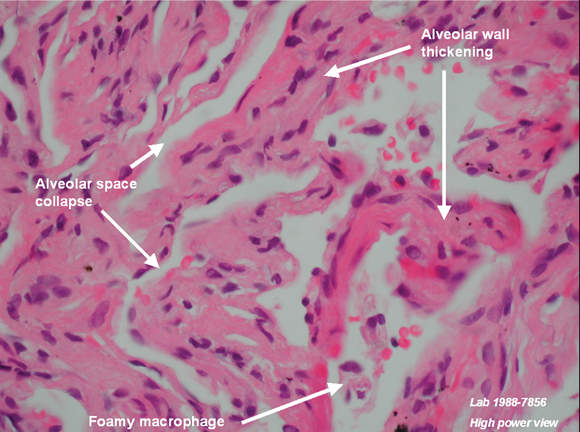

There are also a few reports of lupus-like syndromes, polymyositis/dermatomyositis with lung involvement, and hypersensitivity pneumonitis associated with statin therapy.1-3,6-9 The timing of onset appears unpredictable, with many patients having been taking statin therapy for many months or years before symptoms develop. Clinical features varied in severity from mild dry cough and rash through to severe and progressive respiratory failure. Low-titre antinuclear antibody (ANA) positivity and a raised erythrocyte sedimentation rate were also described in some patients. There are only four reports of open lung biopsy in these cases, two showing hypersensitivity pneumonitis with granuloma formation, one showing diffuse alveolar damage and the other showing non-specific interstitial pneumonitis. Most — but not all — patients responded to drug cessation and therapy with prednisolone or other potent immunosuppressive agents.2,8,9

One previous case of pneumonitis has been reported in the setting of statin therapy, which was confirmed by open lung biopsy, and where the findings closely resembled those in amphiphilic drug toxicity, such as that reported with amiodarone. The authors hypothesised that a toxic mechanism, possibly mediated by statin effects on lipid metabolism, led to the observed intralysosomal lamellar inclusions in pneumocytes and interstitial cells.9 Thus, while not fully characterised, there is a putative mechanism through which statins may cause interstitial pneumonitis.

We thank Dr R Spokes and Dr A Jones, Pathologists, and Dr C Hair, Pathology Registrar, Pathcare Consulting Laboratories, for preparing and annotating histological slides, and Dr D Lun, Radiologist, Barwon Medical Imaging, for providing the high-resolution computed tomography image.